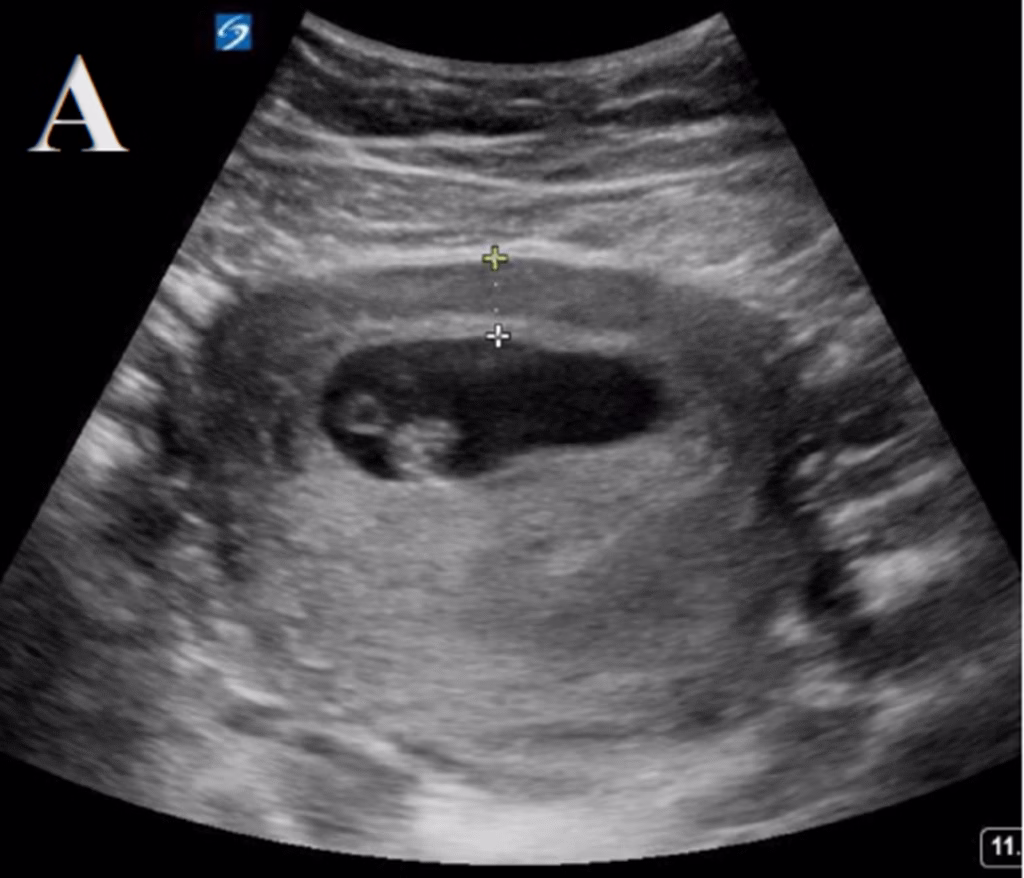

#3 [A]ppendicitis: Is there a non-compressible, blind-ended, large (diameter >6 mm), tubular structure in the RLQ at the point of maximal tenderness, yes or no? These findings are specific for acute appendicitis (Figure 5).

Figure 5. Point of care ultrasound (POCUS) findings with anterior-posterior appendiceal diameter greater than 6mm in longitudinal (A) and transverse (B) views.

Transabdominal Scanning Technique: Either the linear or curvilinear transducer can be used to evaluate appendicitis. While the linear transducer is generally preferred, the curvilinear transducer may provide better visualization through increased depth in patients with greater body mass indices. The ideal transducer placement for identification of the appendix is on the RLQ, particularly at the point of maximal pain or tenderness to palpation. The transducer should be oriented in the transverse plane and the transducer marker should be pointed to the patient’s right shoulder. The anatomic landmarks for identifying the appendix are the psoas muscle and the iliac vessels. The psoas muscle can be seen on the left side of the screen (laterally on the patient) and the iliac vessels will be on the right side of the screen (medially on the patient). The appendix lies anterior to the iliac vessels and will be closer to the top of the screen. The appendix can be differentiated from other structures as it is a blind-ended, non-compressible tubular structure without peristalsis or Doppler color flow.